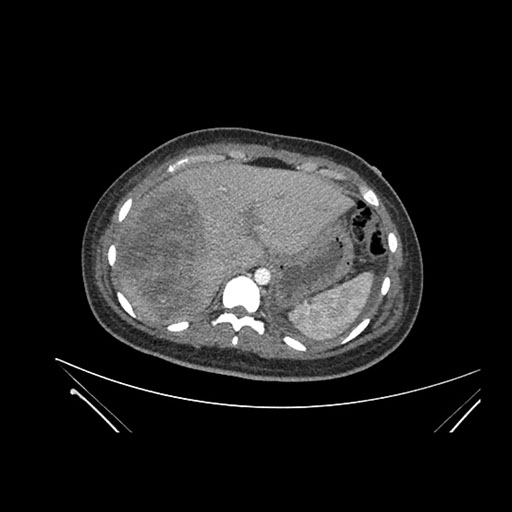

Axial Arterial

Axial Venous

Imaging analysis

Based on initial findings, which issue(s) would you be most concerned about?